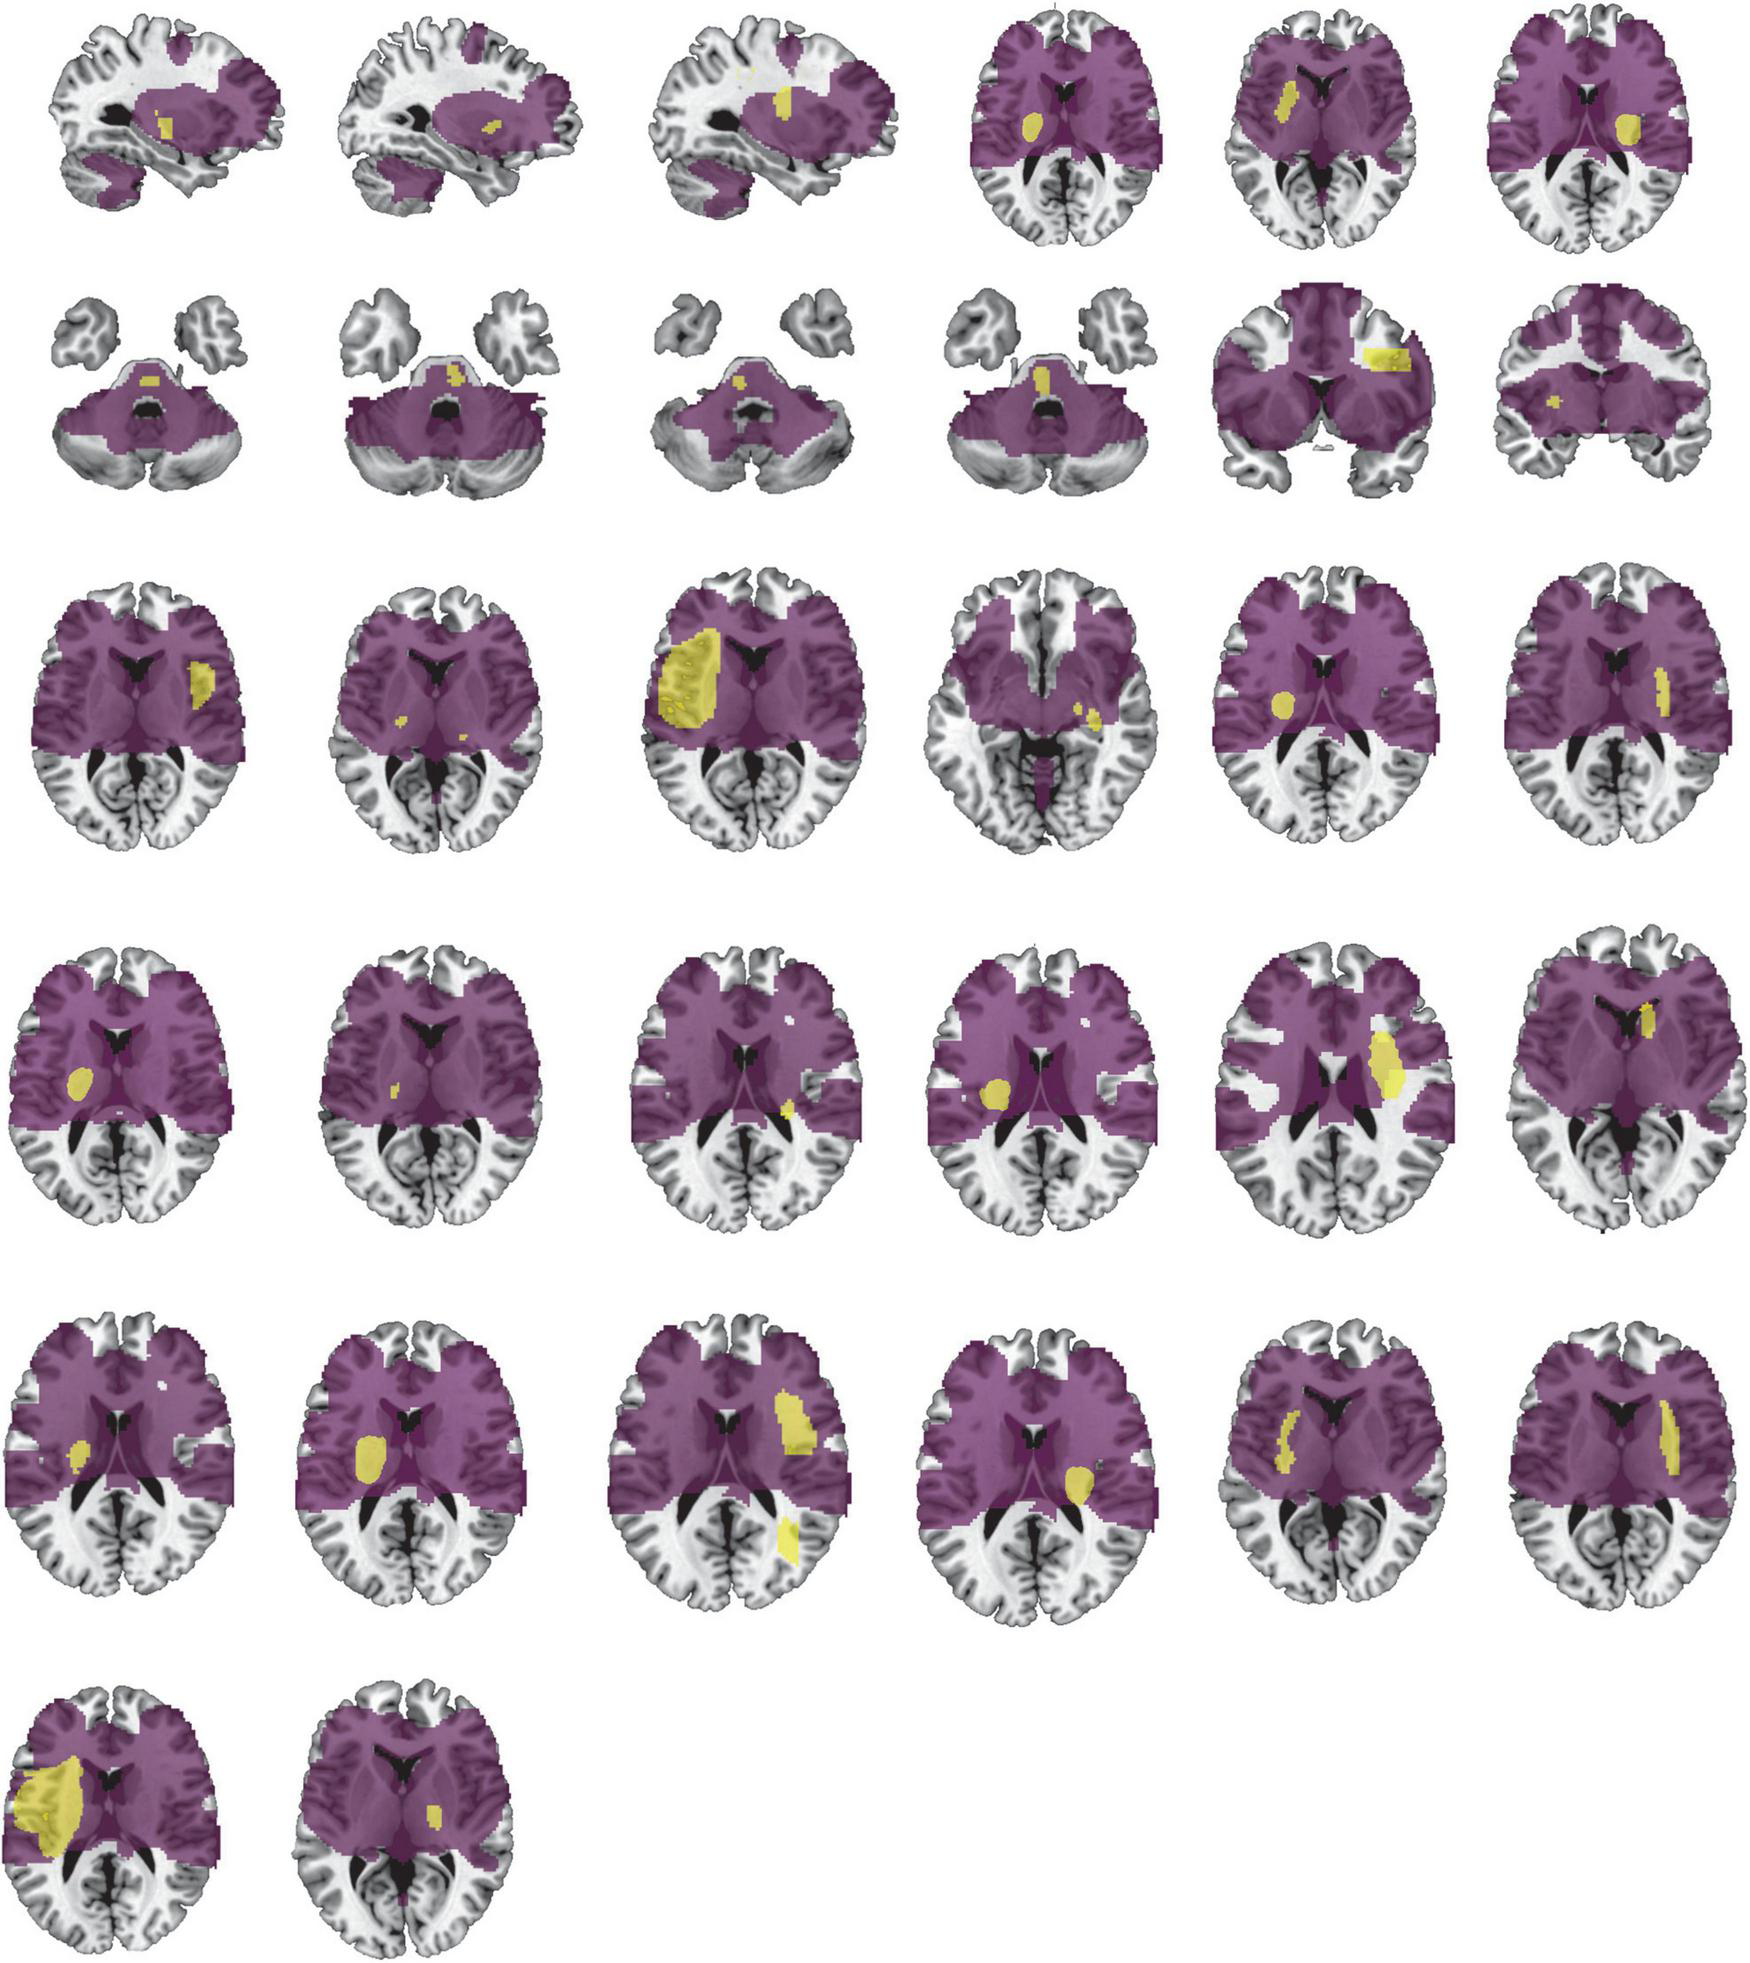

FIGURE 2

Lesion locations causing PSS. The lesions of 32 patients with PSS were manually located on standard brain atlas. All lesions were tracked according to their laterality.

The conjunction analyses determined two ROIs that were both sensitive (connected to > 93% of lesions causing PSS) and specific (voxel presence in both specificity tests) to cause PSS: the right putamen and globus pallidus ROI, and the left putamen and globus pallidus ROI (Figure 3D). According to previous definitions, positive connectivity to these ROIs was defined as a distributed network that encompassed all lesion locations contributing to PSS. For visualization, we performed functional connectivity analysis with the whole brain using these two ROIs as seed points to compute all voxels that were positively connected to the bilateral putamen and globus pallidus. We referred to the final functional connectivity map as the lesion network map of the PSS (Figure 5). For illustrative purposes, the lesion locations were superimposed on the lesion network map. As expected, lesions causing PSS belonged to a common functional connectivity network. The network covered the location of lesions in 31/32 patients identified in our PSS group (Figure 6).

FIGURE 6

Lesion network involves the location of lesions causing PSS. Our lesion network of PSS involves the location of lesions in 31/32 patients identified in the PSS group. Lesions of PSS (yellow) are the same as in Figure 2. The lesion network of PSS is shown in purple.